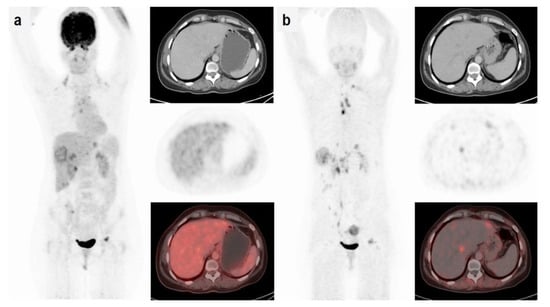

2.3.5. Fibroblast Activation Protein (FAP)

FAP is overexpressed in cancer-associated fibroblasts in the tumor stroma of several types of cancers, including breast, colon, and pancreatic carcinomas. FAP plays a role in tumor invasion and metastasis []. The FAP inhibitor (FAPi) is currently being tested as a cancer therapeutic in clinical trials. Radiopharmaceuticals, such as [68Ga]Ga-FAPI-2 and [68Ga]Ga-FAPI-04, based on FAPi were found to be highly promising as molecular imaging probes []. [68Ga]Ga-FAPI-04-PET/CT and [18F]FDG-PET/CT were compared in 20 female breast cancer patients with primary and recurrent breast cancer in a prospective study []. PET/CT imaging with [18F]FDG and [68Ga]Ga-FAPI-04 were performed in the same week. In detecting primary breast lesions, [68Ga]Ga-FAPI-04 had a higher sensitivity than [18F]FDG (100% vs. 78.2%). PET/CT imaging with [68Ga]Ga-FAPI-04 also showed a significantly higher T/B ratio in breast lesions and in hepatic, bone, brain, and lung metastases (p < 0.05) (Figure 3). Thus, [68Ga]Ga-FAPI-04-PET may offer an advantage over [18F]FDG in delineating tumors to improve diagnosis and help guide FAPi therapy. Kömek et al. suggested that [68Ga]Ga-FAPI-04-PET has an advantage in detecting both primary and metastatic tumors because of its high sensitivity, high SUVmax, and high T/B ratio. Limitations to this trial included the presence of latent bias due to the lack of histological verification on biopsied tissues. Kratochwil et al. found that these tracers could be useful beyond breast cancer []. FAP-targeted PET radiotracers are now considered as potential alternatives to [18F]FDG-PET [,].

Figure 3.

A 52-year-old patient with breast cancer. (a) [18F]FDG-PET/CT showed low or no uptake in the hepatic lesions (SUVmax = 3.9); (b) [68Ga]Ga-FAPI-04-PET/CT showed high uptake (liver metastases SUVmax = 9.1) in all lesions. (Reprinted with permission from Ref. [], 2021, Springer Nature.)